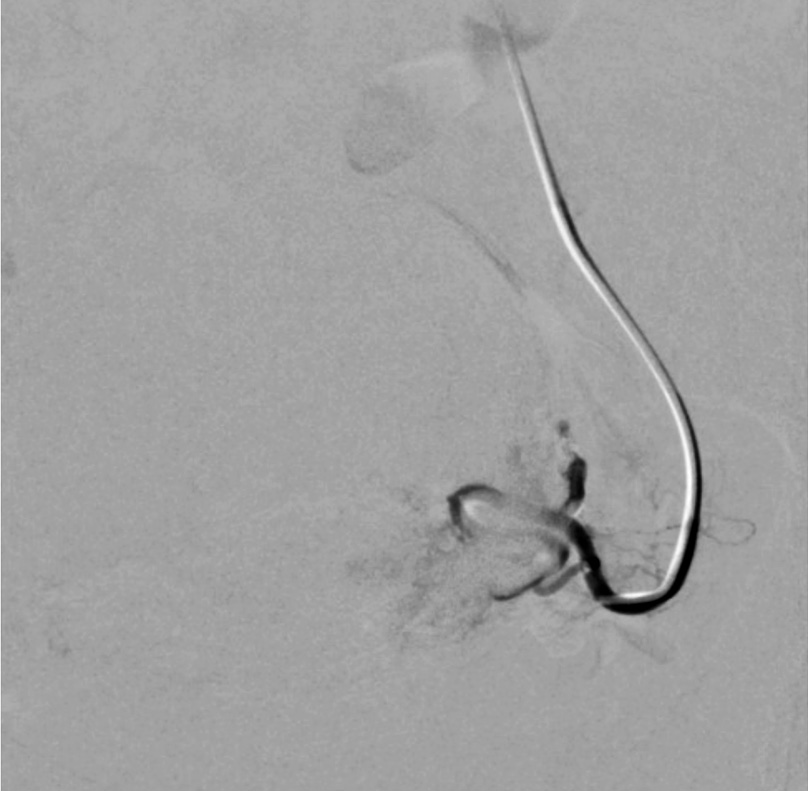

Выполнены пункция и катетеризация правой лучевой артерии в ретроградном направлении. Далее катетером выполнена селективная катетеризация правой и левой маточных артерий. Выявлена миома матки больших размеров с выраженным перифиброидным сплетением. При проведении ангиографии брюшной аорты и таза дополнительных источников кровоснабжения не выявлено. Катетер по проводнику проведен последовательно в горизонтальные сегменты левой и правой маточных артерий, питающих узлы (рис. 2, 3). Проведена эмболизация насыщенными гадотеридолом микросферами до стаза контраста в дистальных сегментах маточных артерий. Рентгеновский контроль эффективности эмболизации – на рис. 4, 5. Катетер и интродьюсер удалены. Наложена давящая асептическая повязка.

Рис. 4. Клинический пример №1. Ангиограмма правой маточной артерии после ЭМА. / Fig. 4. Clinical case 1. Angiogram of the right uterine artery after UAE.

Рис. 5. Клинический пример №1. Ангиограмма левой маточной артерии после ЭМА. / Fig. 5. Clinical case 1. Angiogram of the left uterine artery after UAE.